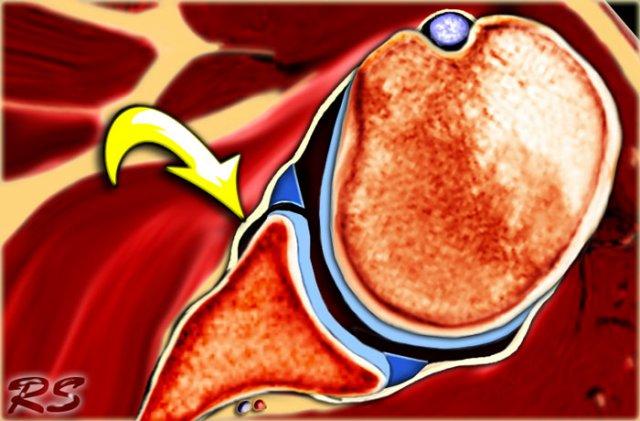

Tổn thương Bankart và các biến thể như Perthes và ALPSA là các chấn thương ở sụn viền trước-dưới.

Các tổn thương này luôn nằm ở vị trí 3-6 giờ vì chúng được gây ra bởi trật khớp ra trước-dưới.

Ngoại lệ duy nhất cho quy tắc này là Bankart ngược, là kết quả của trật khớp ra sau và tổn thương sụn viền sau-dưới.

Bong tách sụn viền trước-dưới (vị trí 3-6 giờ) với rách hoàn toàn màng xương bả vai phía trước, có hoặc không kèm mảnh xương ổ chảo. - Bankart ngược (Reverse Bankart)

Bong tách sụn viền sau-dưới (vị trí 6-9 giờ) với rách màng xương bả vai phía sau, có hoặc không kèm mảnh xương ổ chảo. - Perthes

Bong tách sụn viền trước-dưới (vị trí 3-6 giờ) với màng xương bị bóc tách về phía trong nhưng vẫn còn nguyên vẹn. - ALPSA = Avulsion bao màng xương sụn viền trước (Anterior Labral Periosteal Sleeve Avulsion).

Phức hợp sụn viền-dây chằng bị di lệch về phía trong với hình ảnh vắng mặt sụn viền tại bờ ổ chảo. - GLAD = Tổn thương sụn viền-khớp ổ chảo (GlenoLabral Articular Disruption).

Biểu hiện rách một phần sụn viền trước-dưới kèm tổn thương sụn khớp lân cận.